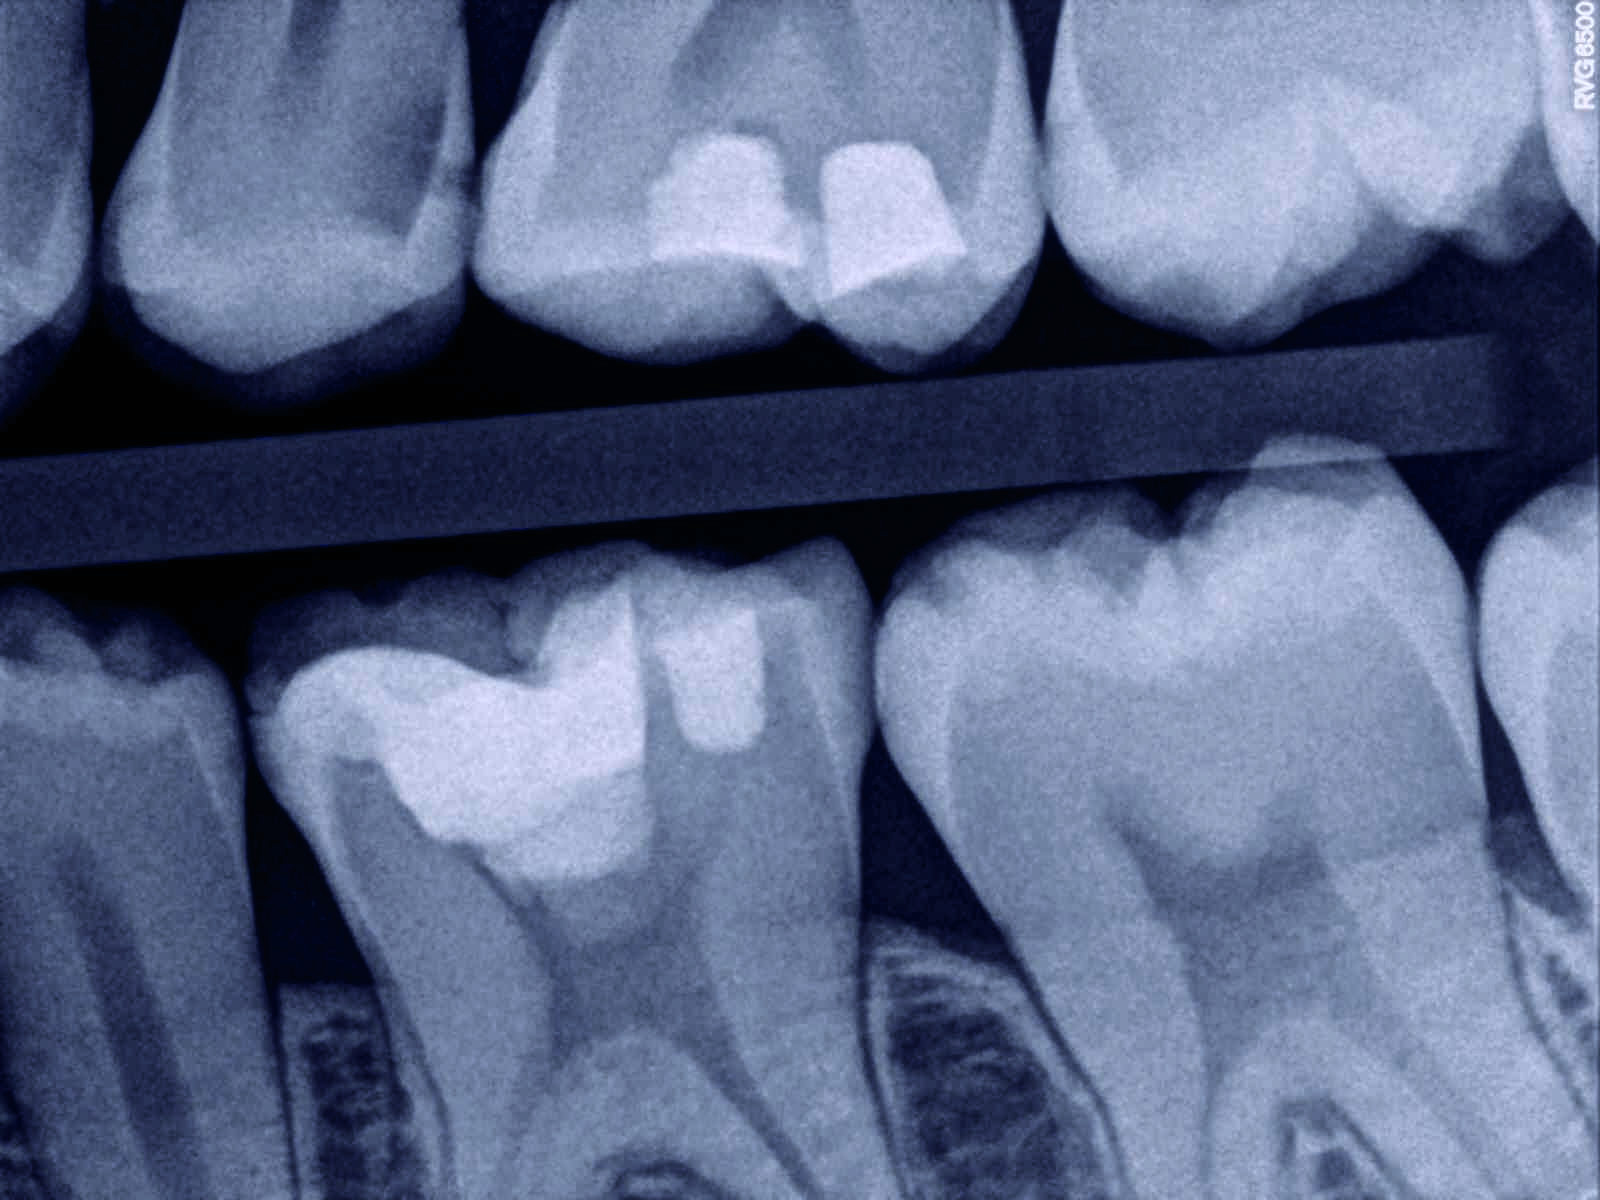

Direct dental pulp capping using calcium hydroxide a 35year followup Direct Pulp Capping Technique Direct pulp capping is used when the pulp is visibly exposed (vital pulp exposure) due to caries, trauma, or iatrogenic insult such as. Confusion and misconceptions surround direct and indirect pulp capping. When a healthy pulp is inadvertently exposed during an operative. Direct pulp capping can be performed when a pulp exposure occurs. This review of the literature provides evidence.. Direct Pulp Capping Technique.